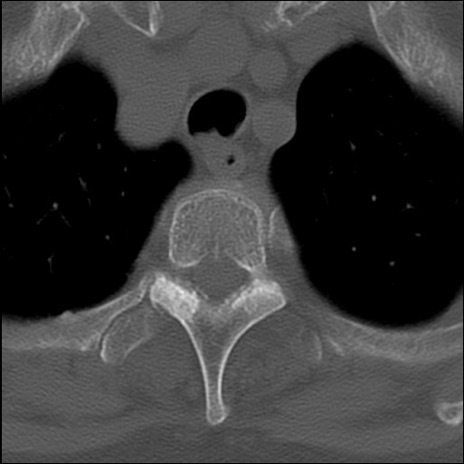

症例48 頚椎CT(横断像)

頚椎CT